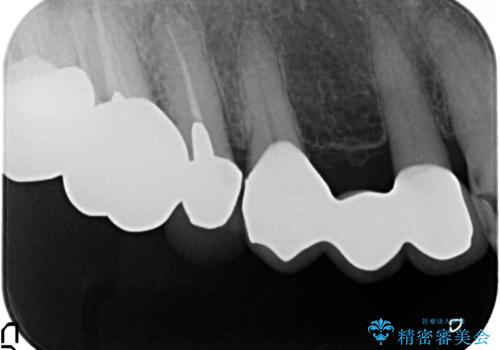

口腔内を精査したところ、右上のブリッジの内側(口蓋側)がかけており、下の前歯(右下1)には唇舌側に瘻孔を伴う大きな根尖病変ができていました。

右上のブリッジ(右上④3②)のやりかえと、下の前歯(右下1)の根管治療を行った後セラミッククラウンによる補綴治療を行いました。

- ¥490,000 (根管治療×1本、土台×1本、仮歯×4本、クラウン×4本)費用は治療当時の料金となります